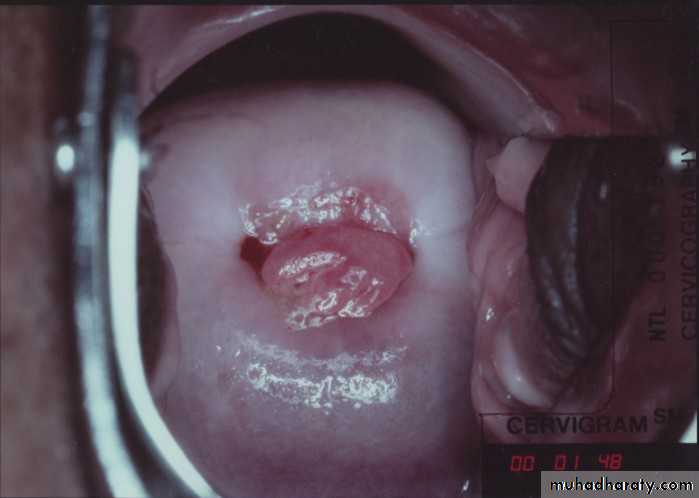

Pelvic examination

Sometimes grape like vesicles of mole may be detected which is confirmation to diagnosis if spontaneous expulsion occurs only.

Causes of vaginal bleeding in early pregnancy:

1. Cervical cause

Ectropion